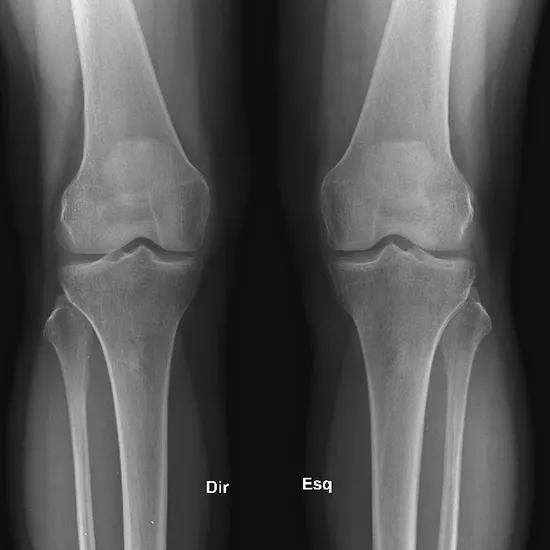

X-ray of the Right Knee AP View

Knee X-rays are an imaging tool used to evaluate the knee joint's alignment, bone quality, and the number of degenerative changes. The AP view is obtained by positioning the X-ray beam in front of the patient.

Doctors recommend this test to detect fractures, injuries, osteoarthritis, and other knee diseases. Knee disorders typically manifest as knee pain, soreness, edema, and deformity.